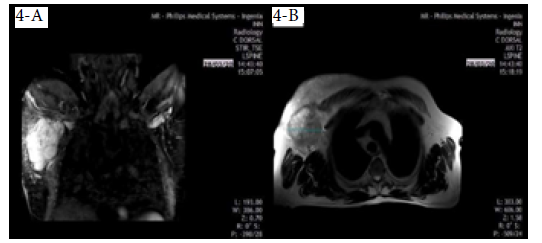

On March 28, 2020, the patient underwent a chest MRI that showed an irregular nodule measuring 9.6x7.4cm, of hyperintense appearance in STIR sequence, with non-circumscribed margins located in the upper outer quadrant of the right breast, extending to the tail of the breast (Figure 4A), and of heterogeneous features in T2-weighted sequences in axial slice (Figure 4B), which did not invade the pectoralis major muscle or the chest wall. Diffuse distortion of the architecture of the right breast was evident in all sequences (BI-RADS 5).

Patient's MRI of the thorax.

Figure 4: Patient's MRI of the thorax.

Source: Image obtained while conducting the study.